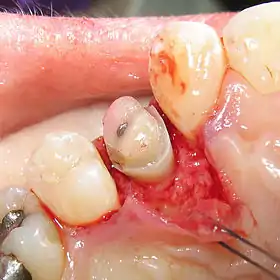

Crown lengthening is a surgical procedure performed by a dentist, or more frequently a periodontist, where more tooth is exposed by removing some of the gingival margin (gum) and supporting bone.[1] Crown lengthening can also be achieved orthodontically (using braces) by extruding the tooth.

Crown lengthening is done for functional and/or esthetic reasons. Functionally, crown lengthening is used to: 1) increase retention and resistance when placing a fabricated dental crown,[2] 2) provide access to subgingival caries, 3) access accidental tooth perforations, and 4) access external root resorption. Esthetically, crown lengthening is used to alter gum and tooth proportions, such as in a gummy smile. There are a number of procedures used to achieve an increase in crown length.[3]

An apically repositioned flap is a widely used procedure that involves flap elevation with subsequent osseous contouring. The flap is designed such that it is replaced more apical to its original position and thus immediate exposure of sound tooth structure is gained. As discussed above, when planning a crown lengthening procedure consideration must be given to maintenance of the supracrestal tissue attachment.

As a general rule, at least 4 mm of sound tooth structure must be exposed at the time of surgery. This, allows for proliferation of the supracrestal soft tissues, which are estimated to cover 2– 3 mm of the coronal root structure thereby leaving 1–2 mm of sound tooth structure supragingivally. Additionally, gingiva tends to regrow over abrupt changes in the bone contour. Therefore, the bone underlying the gingiva and adjacent teeth may need to be recontoured to prevent this.